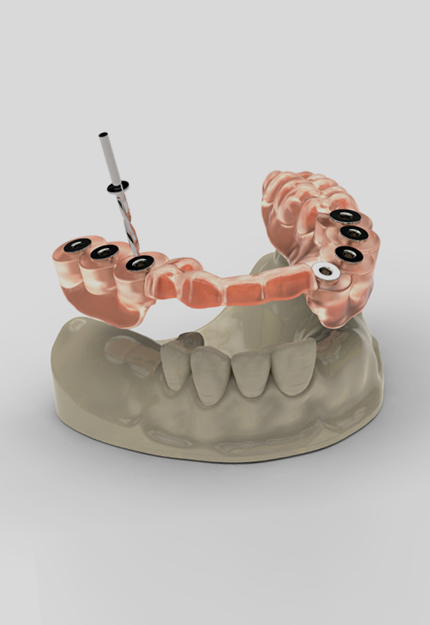

- 임플란트

-

성공적인 임플란트 핵심,

대표원장의 독보적인 임상 노하우와

디지털 진료 시스템 - READ MORE

- 상·하악 풀마우스 임플란트

- 상악 하이브리드 임플란트

- 골조건을 고려한 All-on-4 설계, 치료 후 5개월

- 상·하악 풀마우스 임플란트

- 40대 남성, 치료 후 3개월

- 상·하악 풀마우스 임플란트

- 80대 여성, 치료 후 4개월

- 상악 하이브리드 임플란트

- 골조건을 고려한 All-on-4 설계, 치료 후 5개월

- 상·하악 풀마우스 임플란트